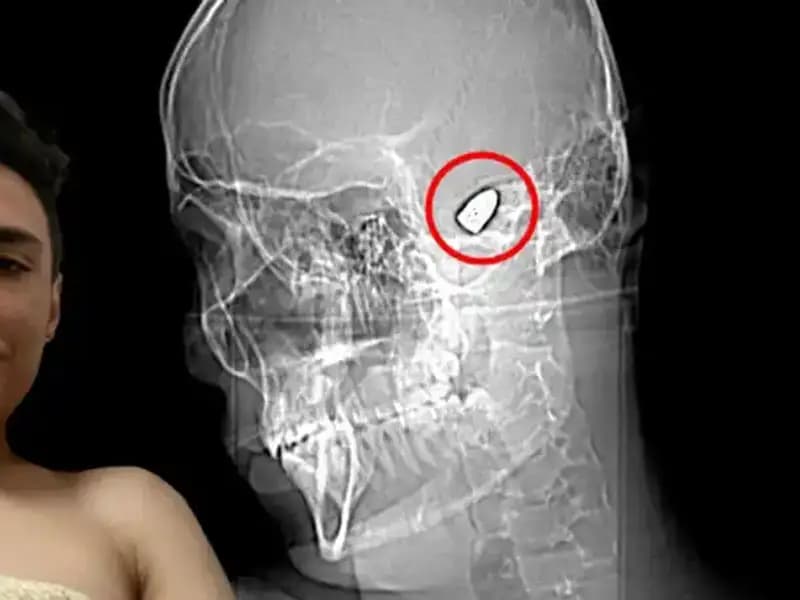

Hayatıyla Yarışan Genç: Kafasında Patlayan Bir Sır VarGenç bir adam, kafasındaki gizemli sorunla her an yüzleşerek yaşam mücadelesi veriyor.